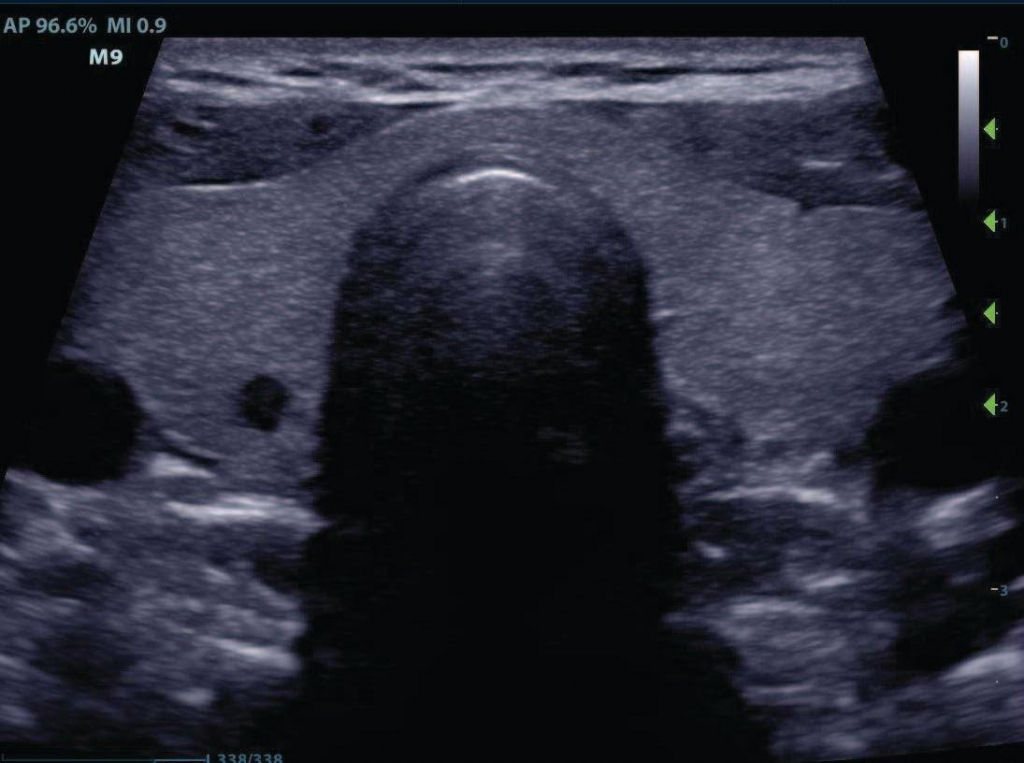

Samsung UGEO WS80A Elite – это сканер премиум-класса нового поколения, в первую очередь рассчитанный на исследования в области акушерства и гинекологии. Аппарат имеет самые передовые инструменты для экспертной оценки самых сложных патологий и при этом удивительно прост в освоении и обращении. UGEO WS80A также является аппаратом, предназначенным для решения самых сложных задач в перенатальной диагностике. Идеально подойдет в качестве "главного" УЗ-сканера в специализированном перенатальном центре.Уникальное качество изображения, инновационные технологии и расширенные возможности объемного ультразвука.

Функция SDMRevo позволяет сканеру визуализировать ткани с меньшим уровнем шума и делать изображения четкими.

Технология Single Crystal улучшает разрешение изображений. От предыдущих моделей UGEO WS80A отличает наличие технологии 5D для проведения более точных исследований.